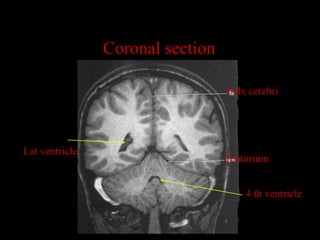

Coronal section Falx cerebri Lat ventricle Tentorium 4 th ventricle

Falx cerebri

Lat ventricle

Tentorium

4 th ventricle